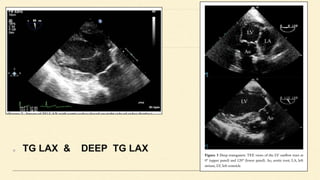

TG long axis

Deep transgastric long axis

TG LAX & DEEP TG LAX

TG LAX &DEEP TG LAX